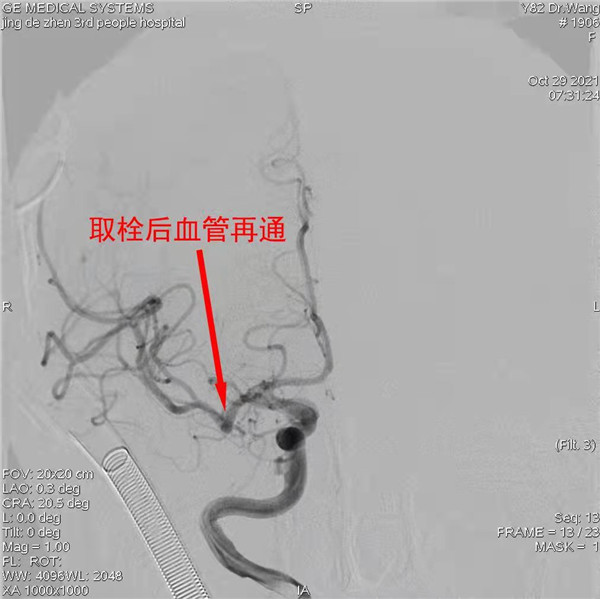

脑卒中是我国第一位死亡原因,同时具有高致残性,严重威胁着人民群众的健康,但该疾病“可防可治不可怕”,发病后及时送院可得到有效的救治。目前,溶栓、取栓治疗实现血管再通是被人为最有效的治疗方式,鉴于该类治疗具有一定风险,实施该类特殊的治疗操作及手术前,需要征求患者及其家属的同意并签署知情同意书后,医生才会进行相关操作。

10月29日是“世界卒中日”,该日凌晨03时30分,景德镇市第三人民医院急诊科接诊了一名家属在外地的82岁急性脑卒中患者,神经内科医师接到会诊通知后,迅速赶到急救室,经过询问病史,高度考虑患者为大面积脑栓塞,该类患者若不经过血管开通治疗,多会卧床甚至死亡,但进行血管开通治疗也面临着巨大的风险。然而时间就是生命,卒中中心迅速开通绿色通道,完善溶栓前检查。该患者为醒后卒中,发病时间不明确,需要完善多模影像学,遂迅速联系影像科,急诊为患者完善了头颅MRI检查,确认患者能从溶栓及取栓治疗过程中可以获益的前提下,积极与患者家属电话联系,电话中征得家属同意后当即给予溶栓并桥接取栓治疗,术后转入ICU进一步监护及治疗,经过积极的治疗,患者偏瘫侧肢体已能自行活动,为患者回归正常生活提供了基础,目前正在进一步积极康复治疗中。